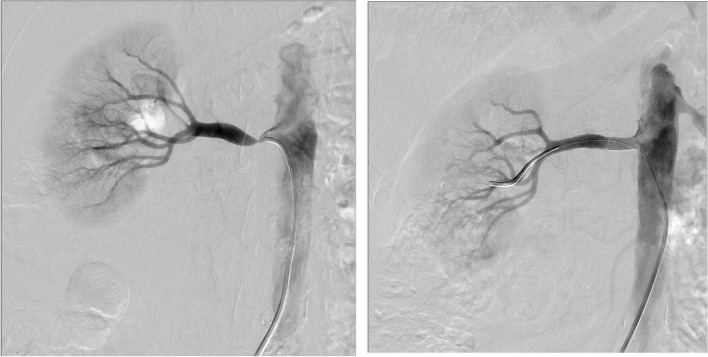

Fig. 1.

Left: Rt renal artery stenosis presenting as severe hypertension (Patient 2). Right: Successful Rt PTRAS with immediate improvement

| 2 | 55 yr old male referred for resistant htn | HTN, IHD, Previous TIA PVD, Smoker | BP: 152/105 mmHg on 3 agents with hypertensive retinopathy | MRA Rt: 90% (10.5 cm) L: 60% (10.5 cm) | Rt PTRAS (Fig. 1) | 1 month: BP < 130/80 mmHg on 3 agents |